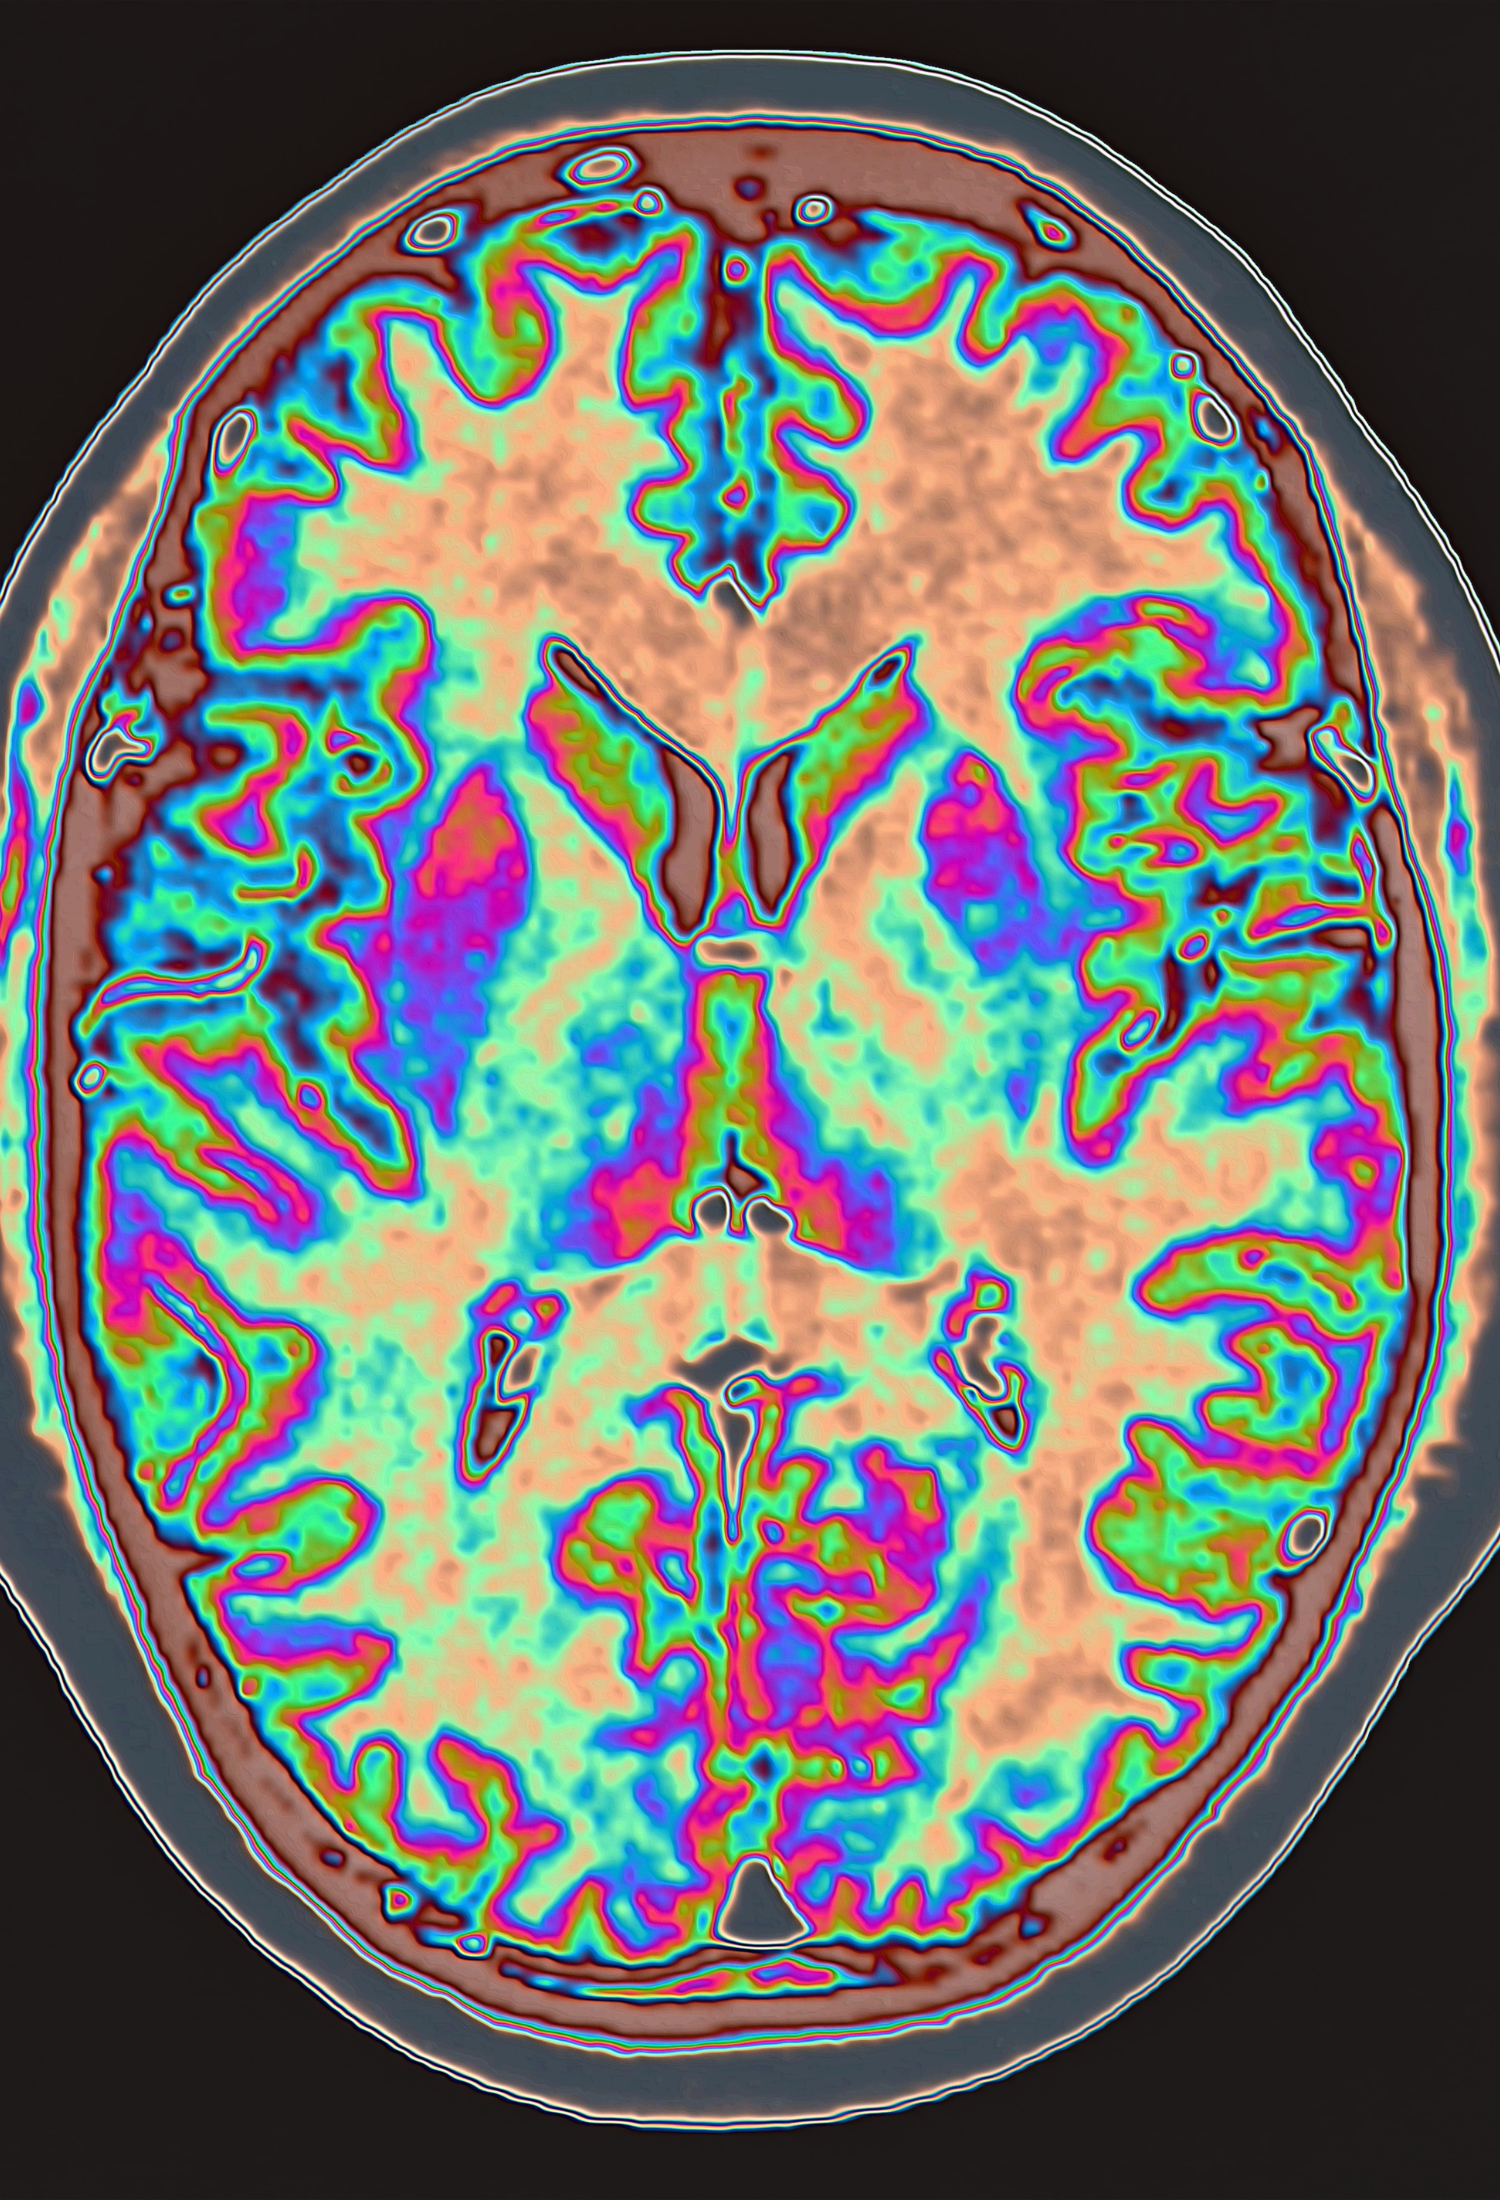

The Epilepsy Imaging Research Group, part of the Nuffield Department of Clinical Neurosciences, use state-of-the-art brain imaging methods, Functional Magnetic Resonance Imaging (fMRI) and Diffusion Tensor Imaging (DTI), to understand how functional networks in the brain respond and adapt to epilepsy and epilepsy-associated lesions.